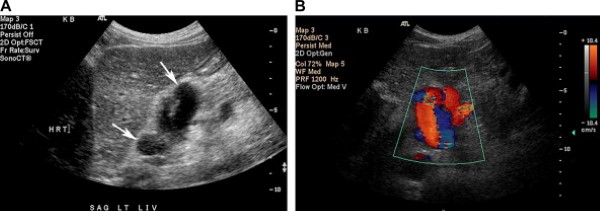

Hình 12. Giãn các tĩnh mạch gan-dạ dày ở bệnh nhân nữ 20 tuổi có tiền sử tăng áp lực tĩnh mạch cửa trong bệnh cảnh viêm đường mật xơ cứng kết hợp với viêm loét đại tràng. (Hình A) Ảnh siêu âm thang xám cho thấy các cấu trúc hình ống, trống âm ở phía sau thùy trái gan tại vị trí nối tĩnh mạch dạ dày – thực quản (mũi tên). (Hình B) Ảnh siêu âm màu cho thấy các cấu trúc đó là các tĩnh mạch giãn ngoằn ngoèo.

Các tĩnh mạch bàng hệ chỗ nối dạ dày-thực quản phát triển từ các nhánh nối giữa tĩnh mạch vành và tĩnh mạch vị ngắn dẫn lưu vào các tĩnh mạch cạnh thực quản và hệ thống của thực quản, rồi đến lượt các tĩnh mạch này dẫn lưu vào hệ tĩnh mạch đơn và bán đơn [1]. Xác định các tĩnh mạch bàng hệ dạ dày-thực quản là quan trọng, bởi vì chúng là nguồn xuất huyết tiềm tàng đe dọa tính mạng khi vỡ. Các tĩnh mạch đó bị giãn, ngoằn ngoèo được nhìn rõ ở vùng dưới niêm mạc đáy vị và chỗ nối dạ dày-thực quản trên các ảnh cắt đứng dọc qua thùy trái gan hoặc giữa bờ cong lớn dạ dày và lách (Hình 12) [2]. Siêu âm Doppler phổ và màu dòng chảy tĩnh mạch cửa bên trong các tĩnh mạch đó xác định chẩn đoán.

Tĩnh mạch cạnh rốn thông (Patent paraumbilical vein)

Tĩnh mạch cạnh rốn (tái thông) là một mạch máu bàng hệ cửa-chủ phổ biến, dễ phát hiện bằng siêu âm trong bệnh cảnh tăng áp lực tĩnh mạch cửa, đặc biệt trong các trường hợp xơ gan do rượu [5]. Tĩnh mạch này đi theo dây chằng tròn trong dây chằng liềm khi nó mang máu từ ngành trái tĩnh mạch cửa tới các tĩnh mạch thượng vị sâu và nông ở thành bụng [1]. Người ta cho rằng tĩnh mạch cạnh rốn thông có thể bảo vệ bệnh nhân khỏi xuất huyết nặng do giãn vỡ các tĩnh mạch thực quản.

Trên siêu âm, tĩnh mạch cạnh rốn có dạng cấu trúc hình ống, trống âm, đường kính ít nhất 3mm, chạy ra trước và xuống dưới từ ngành trái tĩnh mạch cửa hướng tới thành bụng trước. Siêu âm Doppler màu chứng minh phổ dòng chảy tĩnh mạch kiểu một pha [1]. Các tĩnh mạch thành bụng trước giãn ngoằn ngoèo, “hình đầu sứa”, cũng có thể nhìn thấy rõ ở mô dưới da vùng quanh rốn, nhất là khi dùng đầu dò thẳng (Hình 13).

Hình 13. Tĩnh mạch cạnh rốn thông ở bệnh nhân nữ 51 tuổi có tiền sử xơ gan do nghiện rượu. (Hình A) Ảnh siêu âm màu cắt đứng dọc qua thùy trái gan cho thấy một tĩnh mạch to, chạy từ ngành trái tĩnh mạch cửa (đầu mũi tên) đến thành bụng trước (mũi tên). (Hình B) Ảnh siêu âm Doppler màu cắt dọc tĩnh mạch ngoằn ngoèo ở thành bụng trước chạy tới rốn. (Hình C) Ảnh siêu âm Doppler trình bày sóng tĩnh mạch trong mạch máu thăm dò, khẳng định chẩn đoán tĩnh mạch cạnh rốn tái thông.